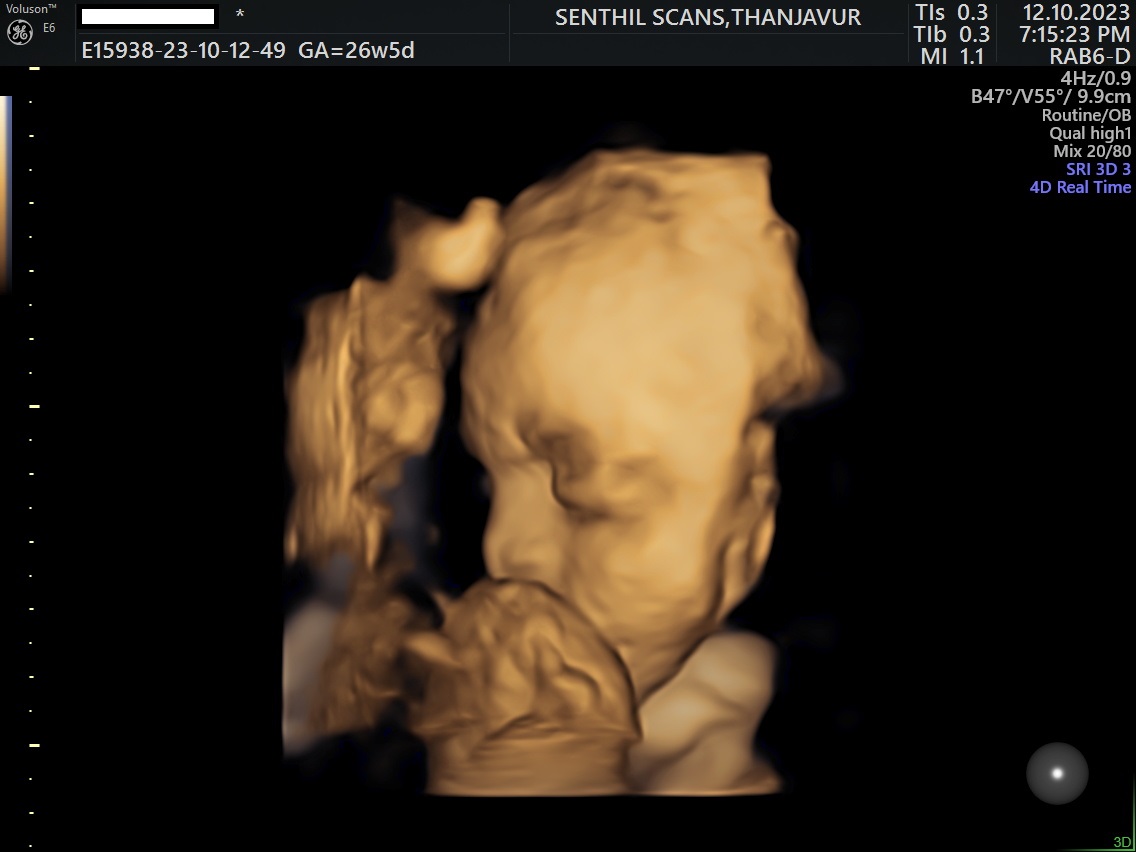

Ultrasound Scan